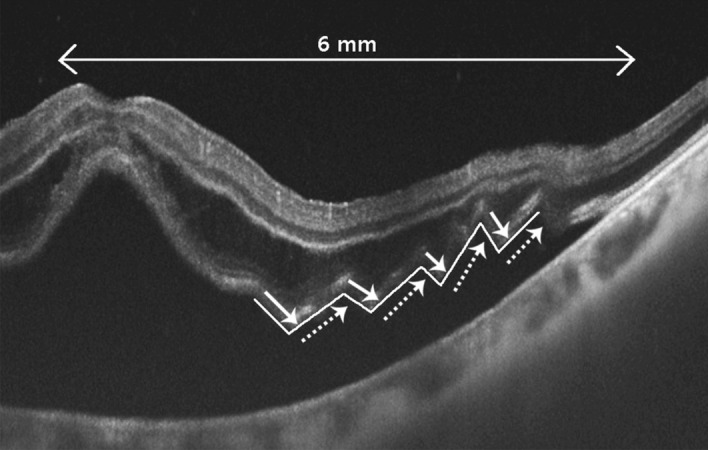

We retrospectively reviewed the electronic medical records of 114 patients (114 eyes) who underwent surgical treatment for RRD and had a follow-up period of at least 6 months at the Keimyung University Dongsan Medical Center between January 2017 and December 2018. This study was performed in accordance with the Declaration of Helsinki and all research was performed in accordance with relevant guidelines/regulations. This study was approved by the Keimyung University Hospital Institutional Review Board (IRB no. 2020-03-037). Informed consent was obtained from all individual patients included in this study. Patients were excluded if they had an uninterpretable OCT, a history of vitrectomy or buckling surgery, or ocular diseases affecting visual acuity and visual field. With swept source OCT (Topcon DRI OCT Triton, SS-OCT, Tokyo, Japan), central macular thickness (CMT), the height of subretinal fluid (SRF), presence or absence of undulation, and ellipsoid zone (EZ) integrity were measured in the preoperative state. CMT was defined as the distance between the umbo and the outer border of the retinal pigment epithelium (RPE). The peak height of SRF was measured between the inner border of the RPE and the highest outer border of the photoreceptor outer segment. These distances were measured perpendicular to the RPE by a ruler in the IMAGEnet 6 (version 1.25; Topcon, Tokyo, Japan) software. Central retinal thickness (CRT) was calculated by substracting the SRF height from CMT. Disruption of the EZ integrity was judged based on the discontinuity of the EZ in OCT. ORU was defined as a change in the outer retinal gradient (negative to positive) of ≥ 3 within a diameter of 6 mm (Fig. 1). Symptom duration was defined as the time between the onset of subjective visual field loss and time of retinal detachment detection on examination. The patients were classified into acute (< 10 days), subacute (10–30 days) and chronic (> 30 days) groups, according to symptom duration.

Figure 1.

Definition of outer retinal undulation (ORU) on preoperative optical coherence tomography; lined arrow: negative directed undulation, dotted arrow: positive directed undulation. The presence of ORU is defined as > 3 combinations of negative and positive undulations (zig zag line).